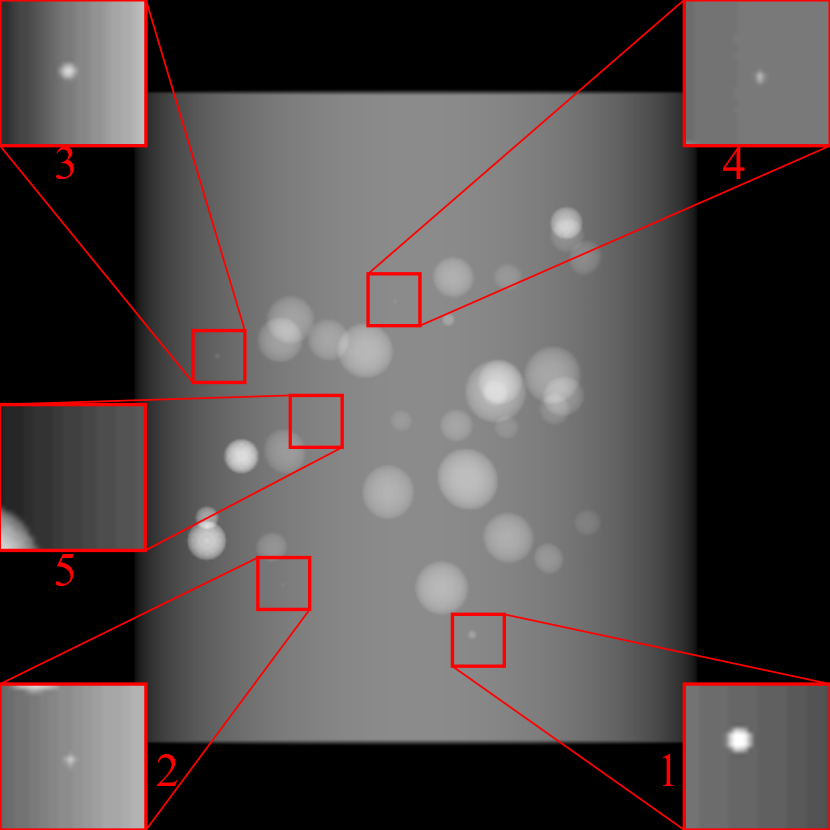

Refer to caption

(a) Orthogonal 0superscript00^{\circ}

(b) Perspective 0superscript00^{\circ}

(c) Perspective deformation ((b)-(a))

(d) Perspective 180superscript180180^{\circ}

(e) Difference of Perspective 0superscript00^{\circ} and 180superscript180180^{\circ}

(f) RGB 0superscript00^{\circ} and 180superscript180180^{\circ}

Figure 6: An example for perspective deformation learning from dual complementary views: (a) the orthogonal projection of the 3D bead phantom from the 0superscript00^{\circ} view; (b) the perspective projection from the 0superscript00^{\circ} view; (c) the difference image between (b) and (a); (d) the perspective projection from the 180superscript180180^{\circ} view; (e) the difference image between (d) and (b); (f) the RGB stack of the 0superscript00^{\circ} and 180superscript180180^{\circ} perspective projection images, where the magenta and green areas correspond to the positive (bright) and negative (dark) areas in (e). The intensity range [0, 11] is converted to [0, 255] for visualization.

Note that when and only when z=0𝑧0z=0, which is m=m=1superscript𝑚𝑚1m^{\prime}=m=1, d180subscript𝑑superscript180d_{180^{\circ}} and dPDsubscript𝑑PDd_{\text{PD}} both equal to 0. This provides a practical way to observe which structures suffer from perspective deformation by assessing deviations between the two complementary views.

The orthogonal and perspective projection images of the same 3D bead phantom in a complementary view setting are displayed in Fig. 6. Fig. 6(c) shows the perspective deformation, which is the difference between the perspective projection (Fig. 6(b)) and the orthogonal projection (Fig. 6(a)) from the 0superscript00^{\circ} view. Fig. 6(c) clearly demonstrates that the magnitude of perspective deformation increases from the center outwards radially. The 180superscript180180^{\circ} perspective projection image is displayed in Fig. 6(d) and its difference with respect to the 0superscript00^{\circ} perspective projection is displayed in Fig. 6(e). Fig. 6(e) is similar to Fig. 6(c) in bead areas, which illustrates that the deviation between two complementary views has strong correlation to perspective deformation. To integrate such dual-view information, like Fig. 5(d), we convert the perspective projections images from the 0superscript00^{\circ} and 180superscript180180^{\circ} views to a 3-channel RGB image in Fig. 6(f). The red and blue channels use images from the 0superscript00^{\circ} view, while the green channel uses images from the 180superscript180180^{\circ} view. In the RGB images, the color reveals the intensity difference between the 0superscript00^{\circ} and 180superscript180180^{\circ} perspective projection images. Grey areas contain close intensity values from both views. Instead, magenta and green areas indicate larger intensity values from the 0superscript00^{\circ} and 180superscript180180^{\circ} views respectively, where perspective deformation correction is necessary. They correspond to the positive (bright) and negative (dark) areas in the difference image in Fig. 6(e). In Fig. 6(f), the magenta beads and their corresponding green beads are located close to each other, which allows a network with limited receptive field size to capture bead-to-bead (point-to-point) dependency.